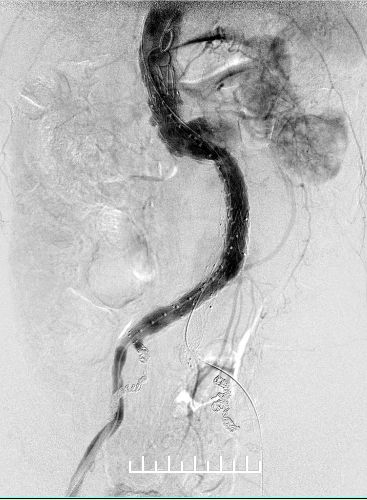

右肾动脉闭塞,精确定位左肾动脉开口释放支架。

左股动脉入路导丝超选短腿失败,经右侧肱动脉使用导丝穿针引线从股动脉引出。

左侧髂动脉送入支架困难,但难不倒我们。

左侧放置第一枚髂腿支架(16mm*140mm,美敦力)

左侧放置第二枚髂腿支架(16mm*140mm,美敦力)

右侧完全释放主体再接一枚16mm-14mm 髂腿支架于髂总动脉近段(美敦力)